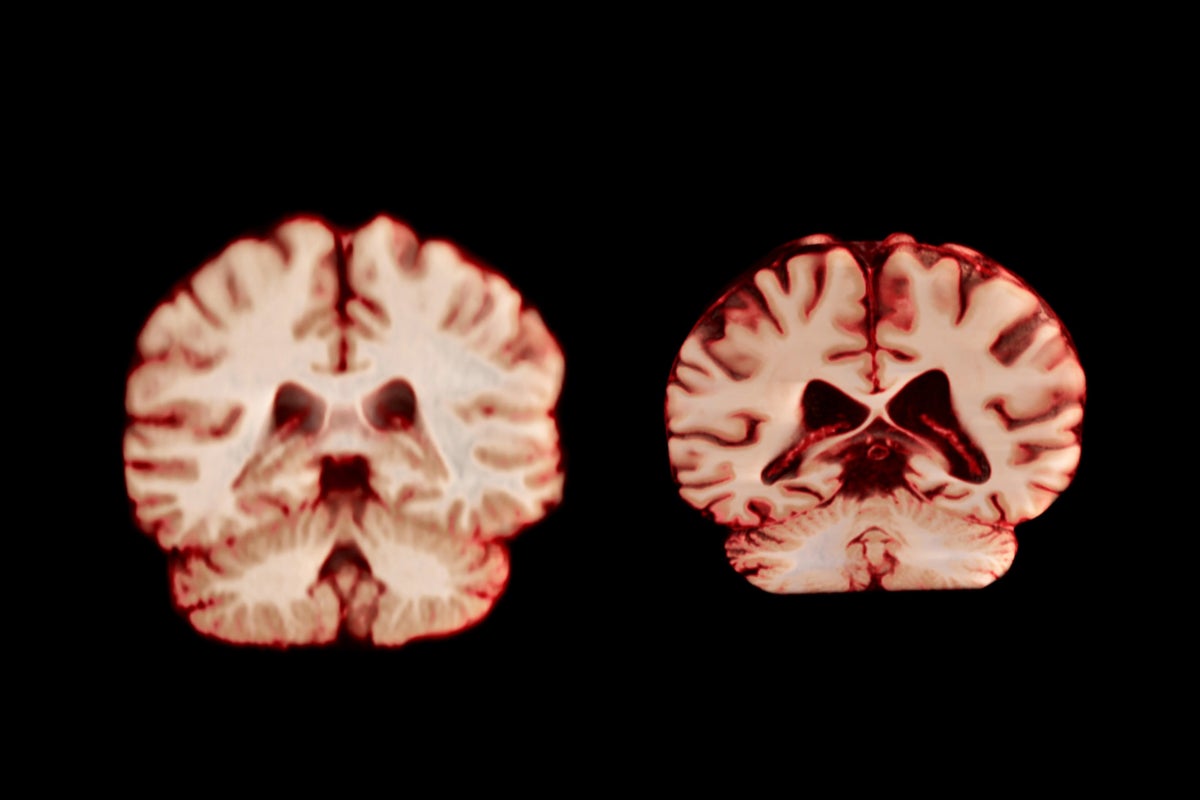

A healthy brain (left) and a brain affected by Alzheimer’s disease.

TheVisualMD/Science Source

During ageing, men experience a greater reduction in volume across more regions of the brain than women do, according to a longitudinal study published today in the Proceedings of the National Academy of Sciences. The authors suggest this means that age-related brain changes do not explain why women are more frequently diagnosed with Alzheimer’s disease than men are.

Overall, men experienced a greater reduction in volume across more regions of the brain than women did. For example, the postcentral cortex, which is responsible for processing sensations of touch, pain and temperature, as well as the body’s own position and movements, declined by 2.0% per year in men and by 1.2% annually in women.

If these changes did have a role in the development of Alzheimer’s disease, the study would have shown that women experience a greater decline in areas associated with the disease, such as the hippocampus and precuneus, which are involved in memory, says Amy Brodtmann, a clinician researcher in cognitive health at Monash University in Melbourne, Australia.